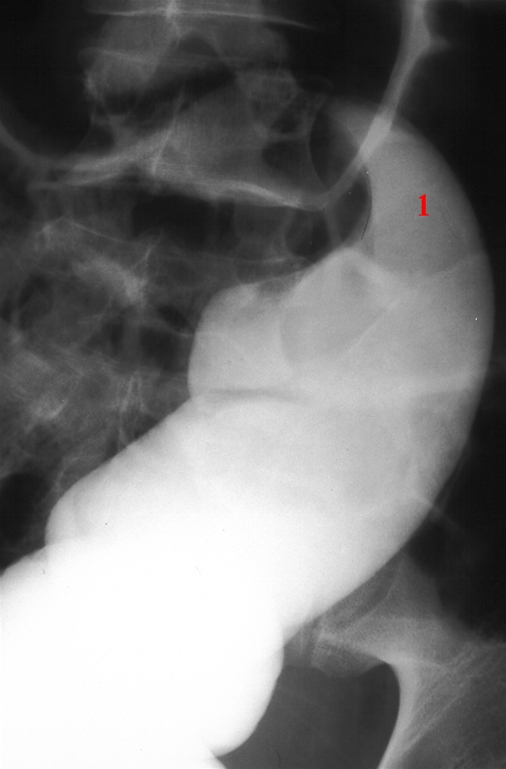

Enkelt kontrast optagelse af rektum-sigmoideumovergangen.

Kontrasten stopper i et typisk "næbformet" udseende (1).